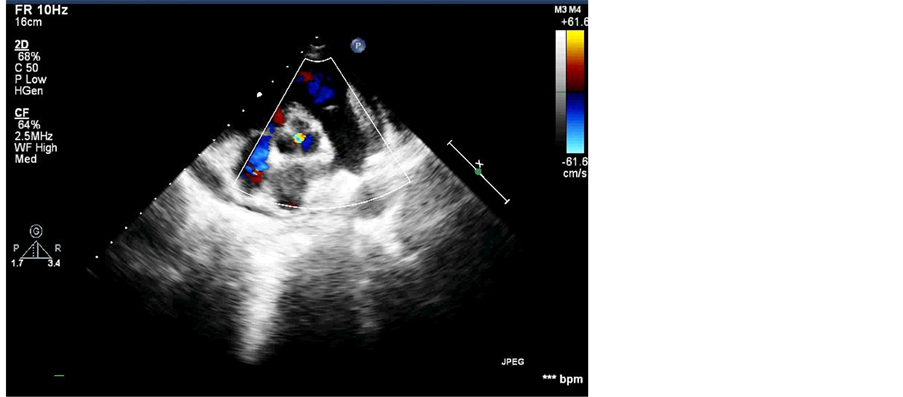

volume overload pattern (Figure 2). Two-dimensional echocardiography confirmed the presence of PDA (8 mm), dilated left ventricle and left atrium due to left to right shunt (>2:1) (Figure 3(A) & Figure 3(B)). Apart from PDA, echocardiogram also revealed the presence of aorta and IVC on left side of spine, anomalous course of IVC (left side of aorta) and mild aortic regurgitation without aortic stenosis (Figure 3(C)). There was a concordant atrio-ventricular and ventriculo-arterial connection. Based upon the findings of echocardiography and physical examinations, we suspected the possibility of isolated levocardia with SI and PDA.

There was no post-procedural complication and echocardiogram also showed no residual shunt (Figure 5).

Figure 3. (A) Echocardiogram in 4 chamber view showing dilated left ventricle; (B) Color Doppler Echocardiogram in short axis view showing patent ductus arteriosus; (C) Echocardiogram showing inferior vena cava lie to the left of aorta.

Figure 5. Post-procedural echocardiogram showing patent ductus arteriosus closure with no residual shunt.